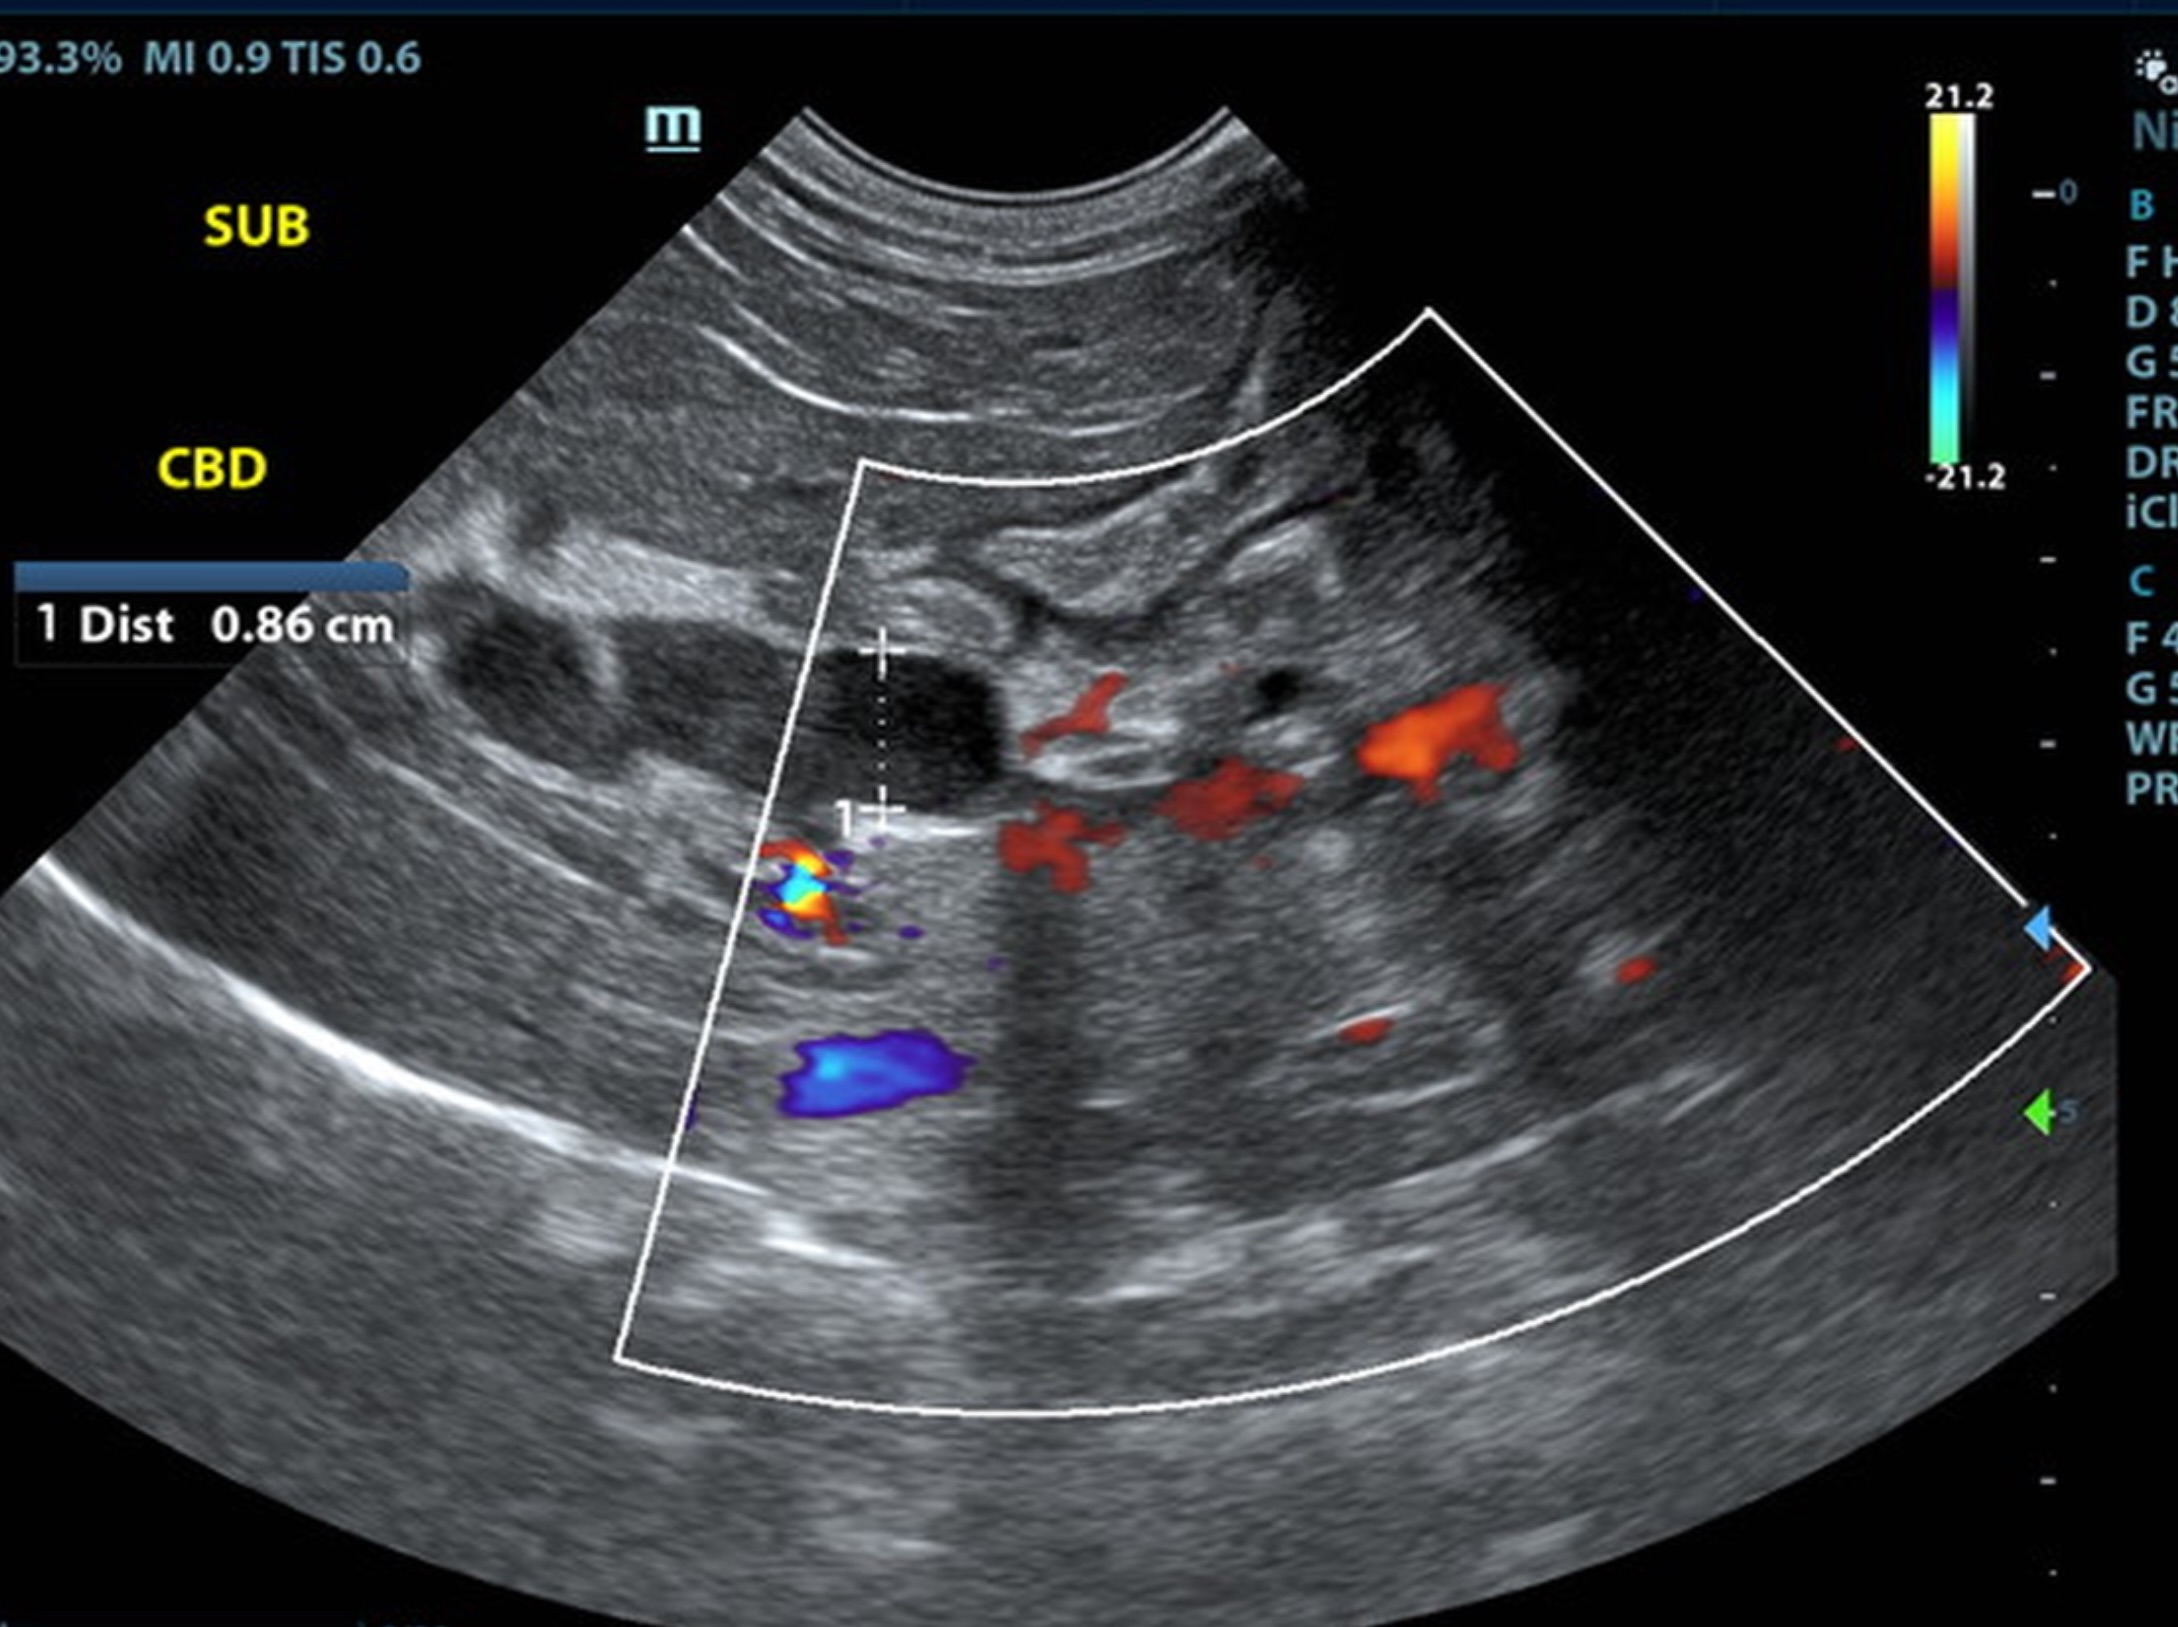

Local biliary duct dilation noted with post hepatic obstruction. Gallbladder was turgid. The common bile duct (CBD) was dilated with echogenic debris or possible tissue proliferation. The CBD measred 0.86 cm. An overt mass was noted at the common bile duct termination, measuring 2.0 cm. Target-type nodules noted in the liver.